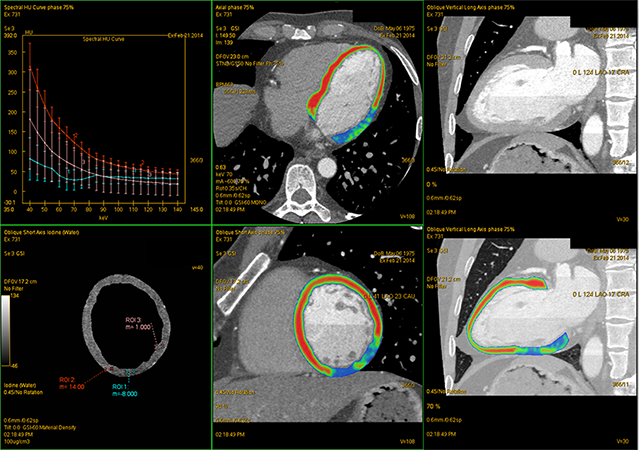

心肌能谱(GSI Myocardium Perfusion) 左室短轴位碘基图及伪彩图:左室下壁及部分外侧壁呈低密度区,能谱曲线呈“U”型相较于正常组织的高斜率正向能谱曲线,提示该区域血流灌注降低,碘定量值分别为-8(缺血区),1(低灌注区),14(正常区)(100ug/cm3);与病变冠脉血供分布区域一致

心肌灌注是评价心肌活性的重要方法。冠脉能谱通过对碘进行定量测定以评估心肌血供。心肌缺血或梗死在碘基图上可显示某个分段的碘含量低于周围组织,提示该部位血流灌注降低或缺失,结合冠脉分支病变,可行解剖和功能同步诊断,指导制定正确的临床治疗方案

CT表现 右冠(RCA)中段完全闭塞 GSI Myocardium Perfusion:左室下壁及部分外侧壁血流灌注降低